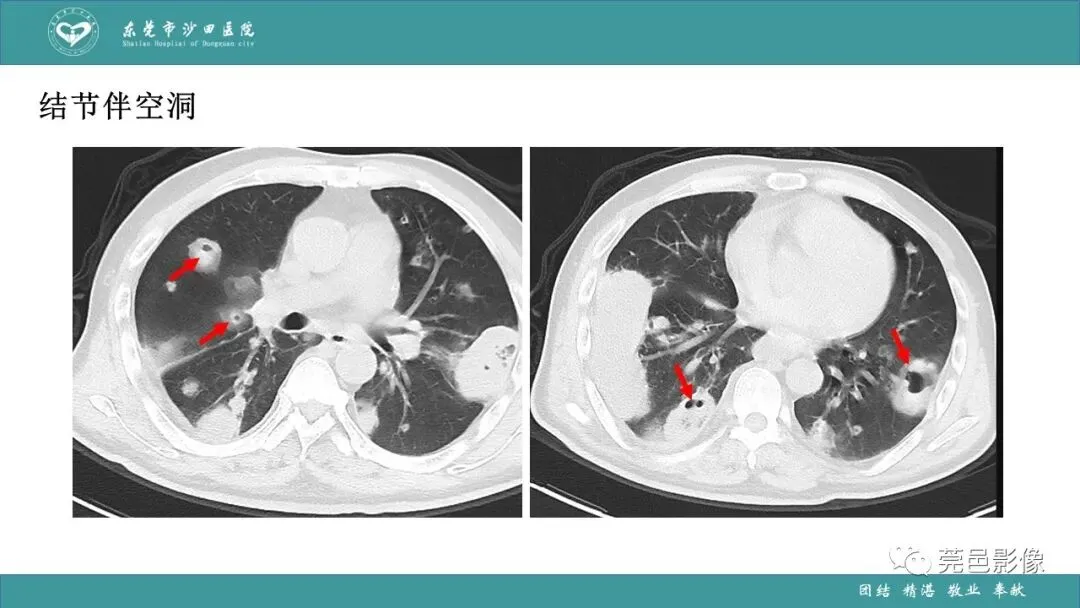

>课件 | 肺炎克雷伯杆菌肺炎影像学诊断与鉴别诊断

课件 | 肺炎克雷伯杆菌肺炎影像学诊断与鉴别诊断